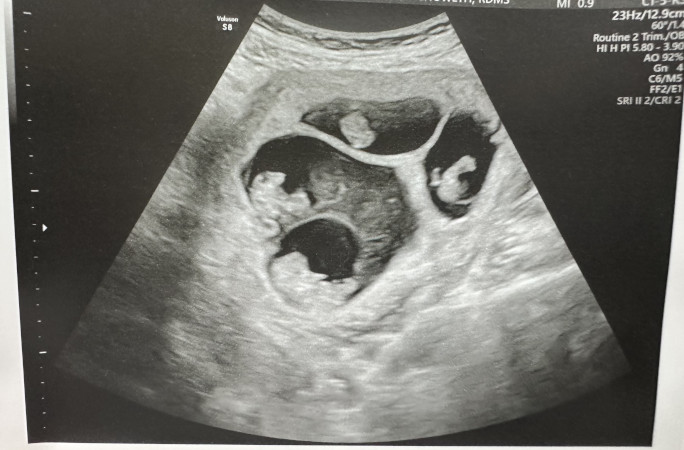

At their first ultrasound appointment, Becca remembers lying on the flatbed with the tech on her right, Lavareis on her left. Although she couldn’t see the screen, her eyes kept flickering between her husband and the examiner, watching their faces as they examined what was in her belly. At first, she thought something was wrong, when their expressions suddenly changed.

“There’s this one big spot, then there’s a little spot, and a little spot. And I was like, 'oh crap, that’s three!'” said Lavareis. “But then the big one was split down in the middle-wise, and she [ultrasound tech] was like there’s one, two, three, four!”

Further examination revealed that Becca was carrying two identical twin girls who shared a placenta (the “one big spot”), while the two boys are fraternal twins with separate placentas (the two little spots).